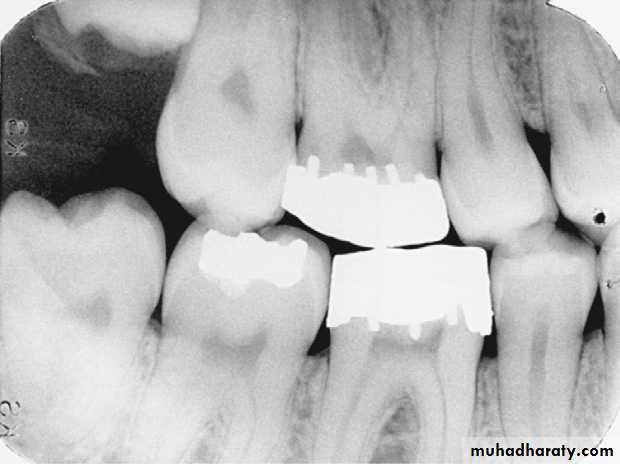

Defective Restorations

Amalgam overhang on the mesial surface of the mandibular first molar.

Ill-fitting restorations and open contacts between teeth contributing to the periodontal condition